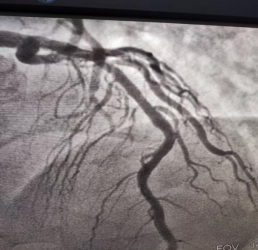

患者張某,男,55歲,自訴近半年在鍛煉身體后反復(fù)出現(xiàn)胸悶不適,休息后癥狀緩解,沒有其他感覺不舒服?;颊哒J(rèn)為可能自己的心臟出現(xiàn)了問題,遂到我院心血管內(nèi)二科就診。接診醫(yī)師詳細(xì)詢問患者病情后,以“急性冠脈綜合征”收住院。入院后完善相關(guān)檢查,與患者及家屬溝通后,行冠脈造影檢查,如下圖(一)

圖一

根據(jù)冠脈造影結(jié)果,康振興主任考慮血管病變局限,鈣化不明顯并且無扭曲,向家屬告知病情,決定置入生物可降解支架,置入后血管完全通暢(圖二),透視情況下僅可見支架標(biāo)記點(diǎn)(圖三),術(shù)后恢復(fù)良好,目前患者康復(fù)出院。